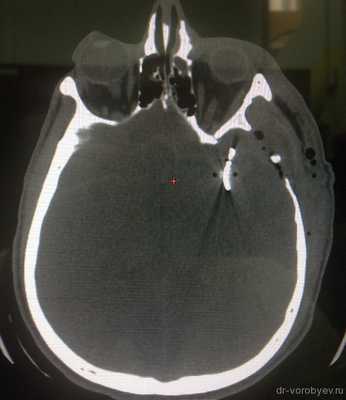

КТ ангиография на следующие сутки после операции. Аневризма выключена. Контрастируются М2 сегменты левой СМА.

Красным кружком отмечена зона вмешательства, где установлены 2 клипса. Имеются признаки ангиоспазма.

На КТ в костном режиме хорошо видна клипса.